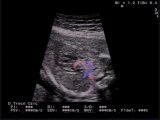

Aloka- Cuore sinistro ipoplasico

Cuore sinistro ipoplasico e persistenza della vena cava superiore sinistra

Cuore sinistro ipoplasico